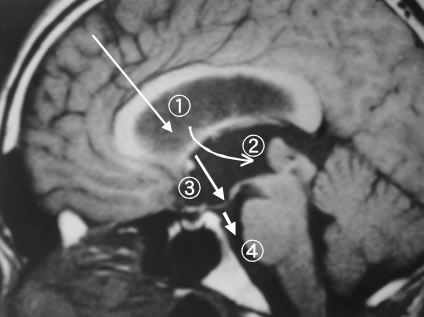

脳室内での使用法で最も頻度の高い治療第三脳室底開窓術です。脳脊髄液は脳室の中で生産され、これは側脳室、第三脳室、第四脳室を通って脳外のクモ膜下腔というところへ流れ出し、最終的に静脈の中へ吸収されていきます。第三脳室の出口にあたる中脳水道という細い通り道が脳腫瘍の圧迫などで閉塞すると、この脳脊髄液の循環が障害され、それより上流にある脳室内に水がたまってしまいます。これを水頭症といいます(水頭症、シャント手術の項参照)。このままでは脳室内圧がどんどんあがって脳を圧迫していくため、圧を逃がしてやるために脳脊髄液の逃げ道を作ってやる必要があります、一つの方法はシャント術(シャント術の項参照)ですが、腹をあけて長いチューブを通す必要があり、腹の中へ液を入れたくない病態(悪性脳腫瘍、癌、腹腔内病変など)や緊急を要する場合には、生理的な脳脊髄液循環を維持するためにこの方法がとられます。やり方は内視鏡を第三脳室内へ挿入し、第三脳室底面の前方にある灰白隆起と呼ばれる薄い膜に穴をあけ、それをバルーンカテーテルで大きく開窓します(図4)。これにより、図3の矢印のように第三脳室内の髄液は脳外のクモ膜下腔(脳底漕)に流れるため、本来の中脳水道を介する経路が必要なくなります。また脳室内を軟性鏡で観察しますと、後方には中脳水道を閉塞する様に腫瘍と思われる組織が確認されます(図5)。腫瘍は鉗子を用いて生検し、病理診断を行います。

図3 MRI矢状断(右:腹側、左:背側)右前頭部より進入し側脳室に入る(1)。モンロー孔を経由し第三脳室に至り後方を観察(2)腫瘍を確認し灰白隆起(3)を穿孔後、脳底槽を観察し(4)手術を終了する。